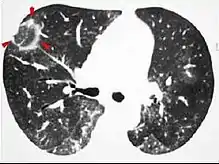

High-Resolution CT image in a patient with Pneumocystis pneumonia infection showing ground-glass opacities.

Inflammation and fibrosis can also cause diffuse GGOs. Pneumocystis pneumonia, an infection typically seen in immunocompromised (e.g. patients with AIDS) or immunosuppressed individuals, is a classic cause of diffuse GGOs. Many viral pneumonias and idiopathic interstitial pneumonias can also lead to a diffuse GGO pattern. Radiation pneumonitis, a side effect of pulmonary radiation therapy, can lead to pulmonary fibrosis and diffuse GGOs.[6]